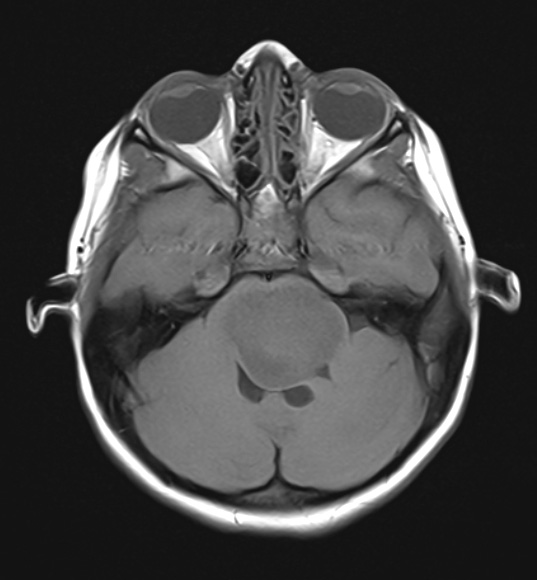

These T1-weighted scans without contrast show a pontine-centered mostly isointense mass occupying almost all of the pons and displacing the cerebellum.